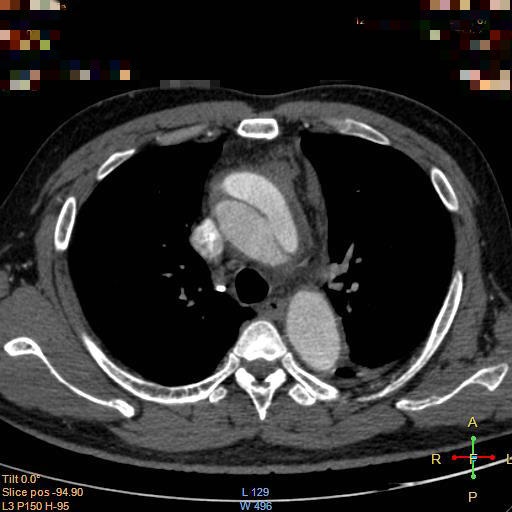

出现此种症状时需要完成的检查包括常规的心电图、心肌酶、凝血功能,上述检查主要用于鉴别诊断,主要与心肌梗塞、肺动脉栓塞相鉴别。明确诊断需要行胸腹主动脉的CTA检查(CT血管成像)。确诊之后需要及时转入血管外科,首先要做的就是镇痛、控制血压和心率,然后依据CTA结果确定患者病变分型,依据分型制定手术方案。

目前有两种分型方式(如上图所示),临床中更常用的是Stanford分型,B型基本可通过覆膜支架的植入完成微创治疗,而A型往往提示病变更复杂,有些患者需要行传统开刀手术,但随着腔内器械及手术技术的提高和创新,目前大多A型病变的患者可通过烟囱、开窗或者分支支架的方式完成腔内治疗,极大降低了手术创伤和风险,提高了患者生存率。